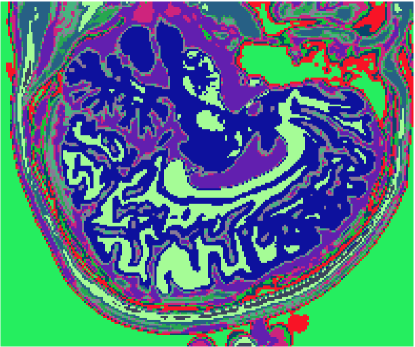

A figura 6 mostra os resultados de classificação, enquanto a figura 7 exibe os resultados de quantização para a imagem sem ruído da fatia 97, figura 5, usando os métodos KO, CM, KM, ODC-PME e ODC-CAN. Esses resultados ilustram qualitativamente as diferenças entre os métodos de classificação e quantização, dado que a fatia 97 possui todas as 13 classes presentes na análise [51].

Figura 6: Composição colorida R0-G1-B2 das imagens da fatia 97 ponderadas em PD, T1subscript𝑇1T_{1} e T2subscript𝑇2T_{2} (a) e resultados de classificação usando os métodos KO (b), CM (c), KM (d), ODC-PME (e) e ODC-CAN (f)

A tabela 2 mostra os resultados da avaliação dos métodos de classificação não supervisionada quanto à quantização vetorial, usando os índices de fidelidade ϵMEsubscriptitalic-ϵME\epsilon_{\textnormal{ME}}, ϵMAEsubscriptitalic-ϵMAE\epsilon_{\textnormal{MAE}}, ϵMSEsubscriptitalic-ϵMSE\epsilon_{\textnormal{MSE}}, ϵRMSEsubscriptitalic-ϵRMSE\epsilon_{\textnormal{RMSE}} e ϵPSNRsubscriptitalic-ϵPSNR\epsilon_{\textnormal{PSNR}}, considerando todas as 181 fatias com 3 bandas (DP, T1subscript𝑇1T_{1} and T2subscript𝑇2T_{2}), para os métodos KO, CM, KM, ODC-PME e ODC-CAN e 0% de ruído. Já os gráficos das figuras 8, 9, 10 e 11 mostram os resultados em função do nível percentual de ruído para os diversos métodos, para um total de 6 volumes de 181 fatias de 3 bandas, totalizando 1086 imagens coloridas, ou 3258 imagens em níveis de cinza.

Figura 7: Composição colorida R0-G1-B2 das imagens da fatia 97 ponderadas em PD, T1subscript𝑇1T_{1} e T2subscript𝑇2T_{2} (a) e resultados de quantização usando os métodos KO (b), CM (c), KM (d), ODC-PME (e) e ODC-CAN (f)